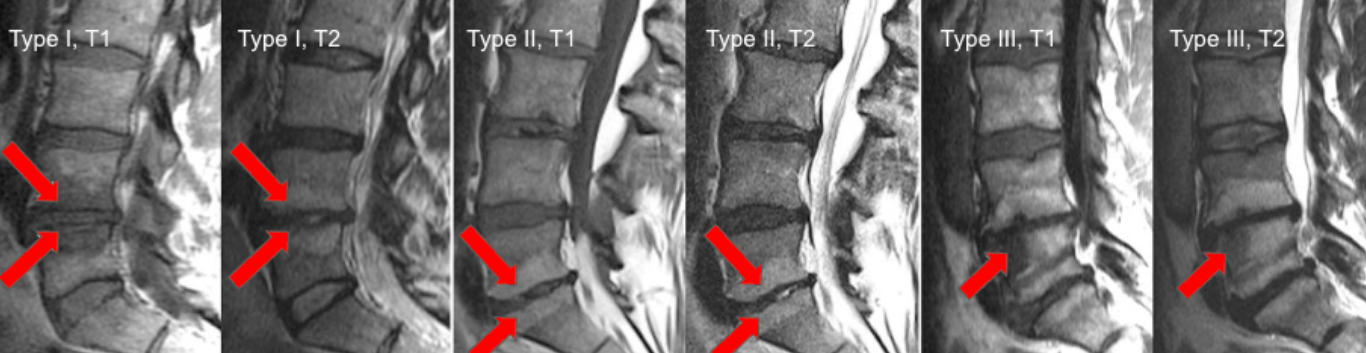

Modic Endplate Changes (Type I, II, III)

Modic changes describe signal intensity alterations of vertebral body marrow adjacent to degenerated intervertebral discs, reflecting different stages of the degenerative cascade. They are strongly associated with disc degeneration, low-back pain, and segmental instability.

Three distinct patterns are recognized based on MRI signal characteristics.

• Type I: T1 hypointense, T2 hyperintense; edema / active inflammation

• Type II: T1 hyperintense, T2 iso-/hyperintense; fatty marrow replacement

• Type III: T1 hypointense, T2 hypointense; subchondral sclerosis